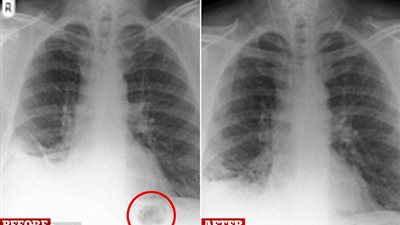

تمكن الأطباء من بناء لسان امرأة بريطانية، باستخدام جزء من ذراعها، بعدما تسبب مرض السرطان في قطع جزء كبير من لسانها، حيث استعادت قدرتها على النطق. بدأت مشكلة هيذر جونسون البالغة من العمر 29 عامًا، وهي ...